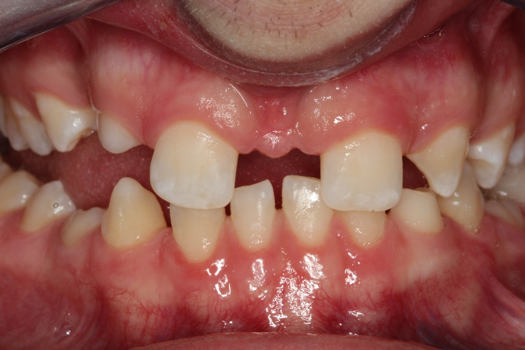

Fig 10. Photograph, 25-year-old brother.

Figure 10

Figure 5 through Figure 12 exemplify what currently may present in private dental practices with these types of patients. Four brothers aged 14 years to 27 years all suffered from obstructed airways; high incidence of caries of dentin, enamel, and cementum; moderate periodontal disease; collapsed vertical; undiagnosed OSA; and the potential for increase in comorbidities such as diabetes, cardiovascular disease, dementia, cancer, high blood pressure, and others. Symptomology was presented throughout the young lives of the brothers in this family. The parents were unaware that the dental agenesis and premature permanent tooth extraction could have led their sons into severe health issues as they matured.

Swift intervention took place with caries control, periodontal care, orthodontic evaluation for arch form development to aid in the development of facial bones and creating an improved upper airway with nasal patency. These interventions were followed up with definitive implant therapies and rapidly advancing restorative technology and materials. Thus, not only were these young men's smiles restored, they also were provided with the opportunity to regain their dignity when they become confident with their new smiles.